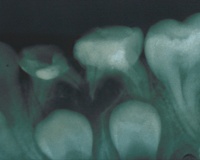

Чтобы уточнить вид хронического периодонтита, делают рентгенографию зуба с окружающими его тканями:

- При гранулирующей форме заметен очаг разрежения кости, нарушения целостности кортикальной пластинки с нечеткими границами.

- Гранулематозный вариант характеризуется четко ограниченной зоной поражения круглой или овальной формы.

- При фиброзном периодонтите врач выявляет расширение щели в апикальной области.